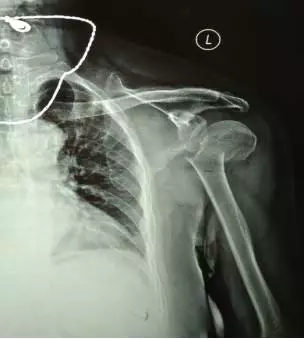

70多歲的鮑阿婆在家人陪同下來(lái)到上海大團(tuán)醫(yī)院就診。大團(tuán)醫(yī)院的醫(yī)生給鮑阿婆左肩部做了X線片檢查。片子拍出來(lái)竟然是左肱骨近端粉碎性骨折。外科頸,大結(jié)節(jié)都碎了,而且骨折端移位很嚴(yán)重。

正骨科的虞杰主任、邵鵬及葉華磊醫(yī)生看到鮑阿婆的片子也是一皺眉頭,這么厲害的骨折,還真是少見,而且移位這么嚴(yán)重,手法復(fù)位的難度也是相當(dāng)大的。不過(guò)患者的信任給了他們很大的動(dòng)力,即使困難也要盡力幫患者。

整復(fù)前